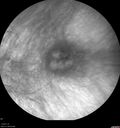

82 year old female with asymptomatic nevus in the left eye followed for 3 years without change.

Choroidal Nevus with Drusen404 views82 year old female with flat nevus for 3 years.00000